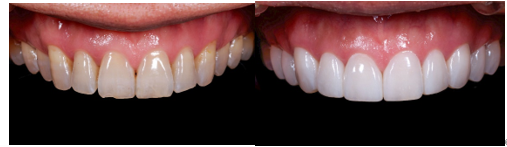

オリジナルラミネート「プラチネート」

【治療ケース1 プラチネート10個】

【担当医からのポイント】 この患者様は、横顔(Eライン)で際立つ歯列の乱れを長年気にされており、それが日常的なコンプレックスとなっていました。不調和な歯の形とトーンの暗さが大きな悩みで、笑う際に口元を手で覆う癖がおありでした。

当院では、単に歯を白くするだけでなく、患者様の肌色やリップライン、全体の雰囲気に溶け込む、極めて自然な仕上がりを目指しました。

その実現のため、作製する補綴物の透過性(透明感)、輝度(明るさ)、そして形態を、1ミリの狂いもなく緻密に調整し、作り込んでいきました。

特に前歯の治療においては、顔の中心線とのバランスが肝心です。正面の見た目だけでなく、側方から見た際の立体感や、自然な曲線美までもデザインに落とし込みました。歯の並びと長さを細やかに整え、調和の取れた美しいスマイルラインを形成しました。人工的で不自然な印象は徹底的に避け、品格のある、均整の取れた口元へと導きました。

治療後は、自然な明るい笑顔を取り戻され、「以前より格段に自信を持って笑えるようになった」と、大変ご満足いただけました。